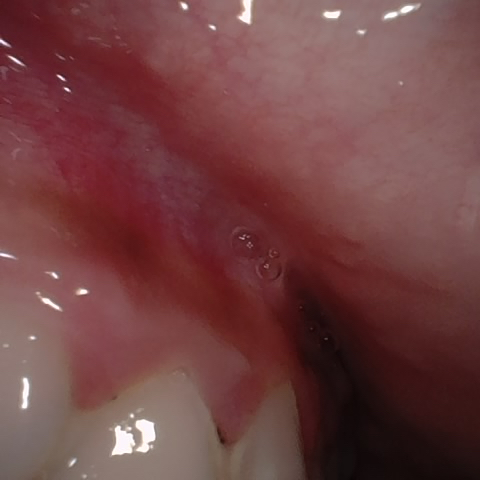

NHD30572

Annotated as "Good"